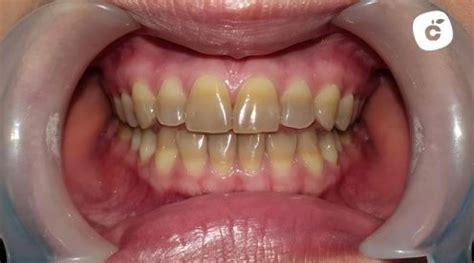

Tinciones por tetraciclina antes y después del tratamiento de blanqueamiento.

- Efectividad en tinciones específicas: El blanqueamiento dental está indicado en ciertos tipos de tinciones, como las producidas por tetraciclina (tipos I y II), debido a la menor gravedad de las tinciones. En estos casos, es más efectivo realizar el blanqueamiento dental en consulta, continuado con un tratamiento ambulatorio, ya que estas tinciones están más relacionadas con la dentina.